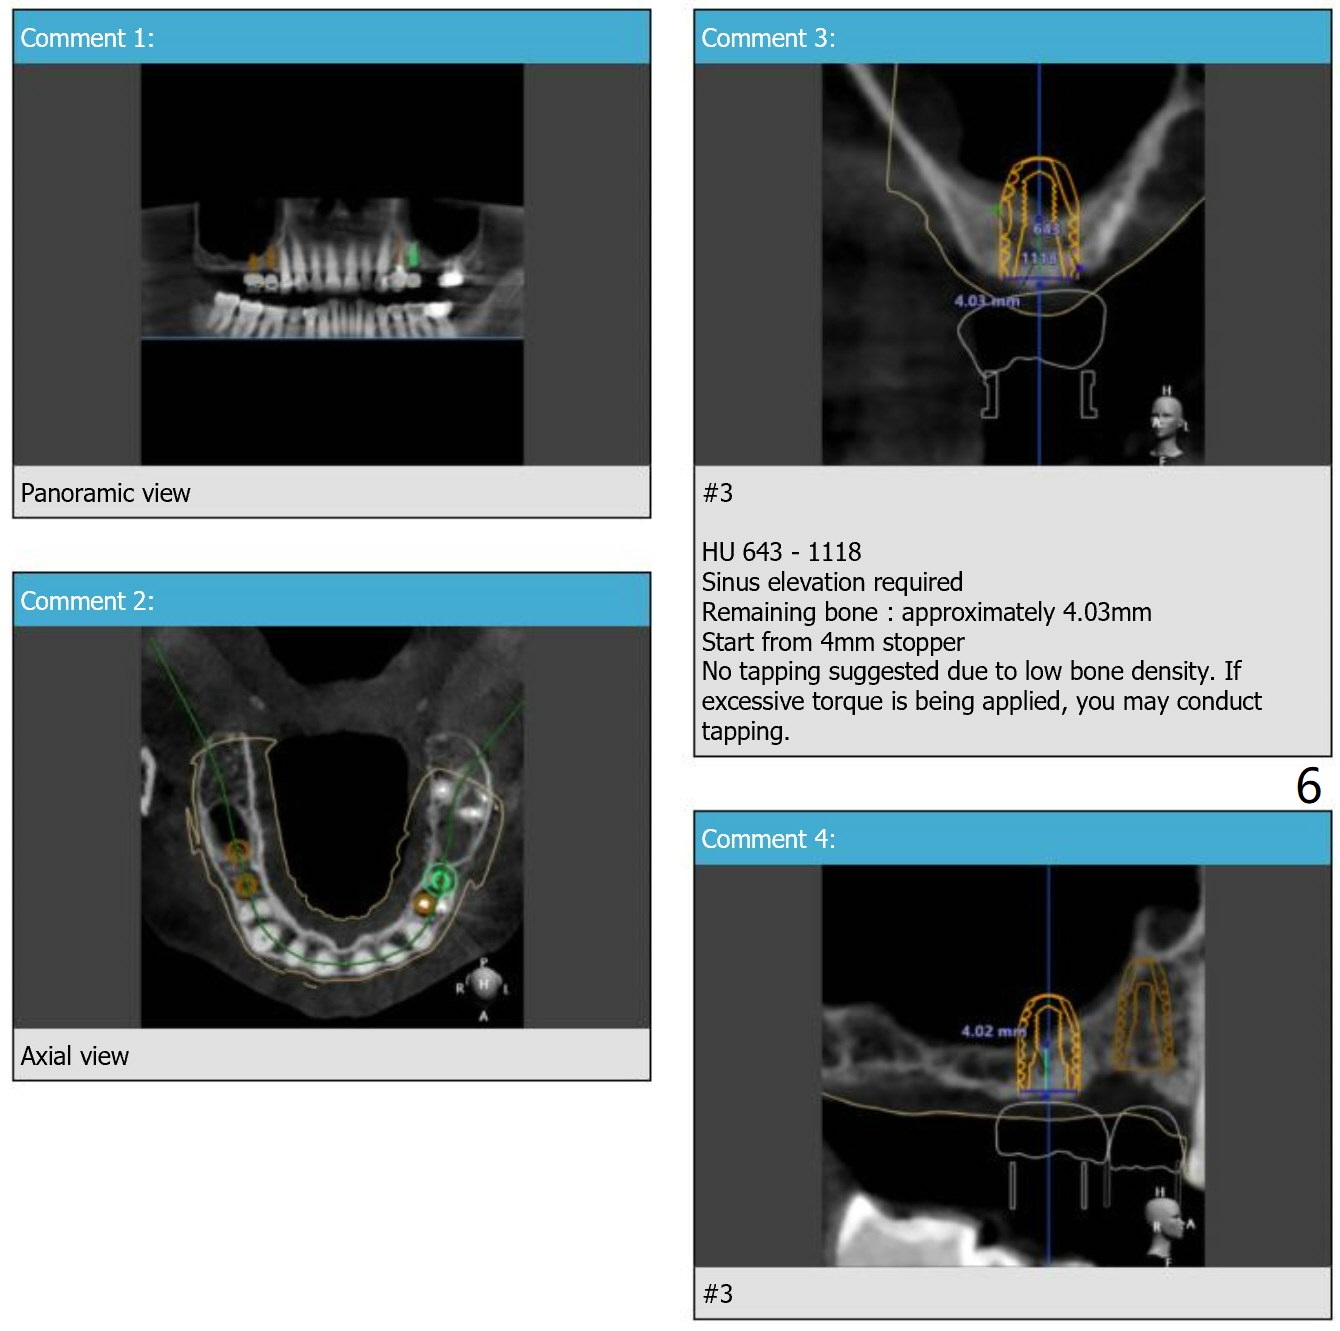

Guide for Sinus Lift

Return to Upper Arch Immediate Implant, Trajectory, No Antibiotic